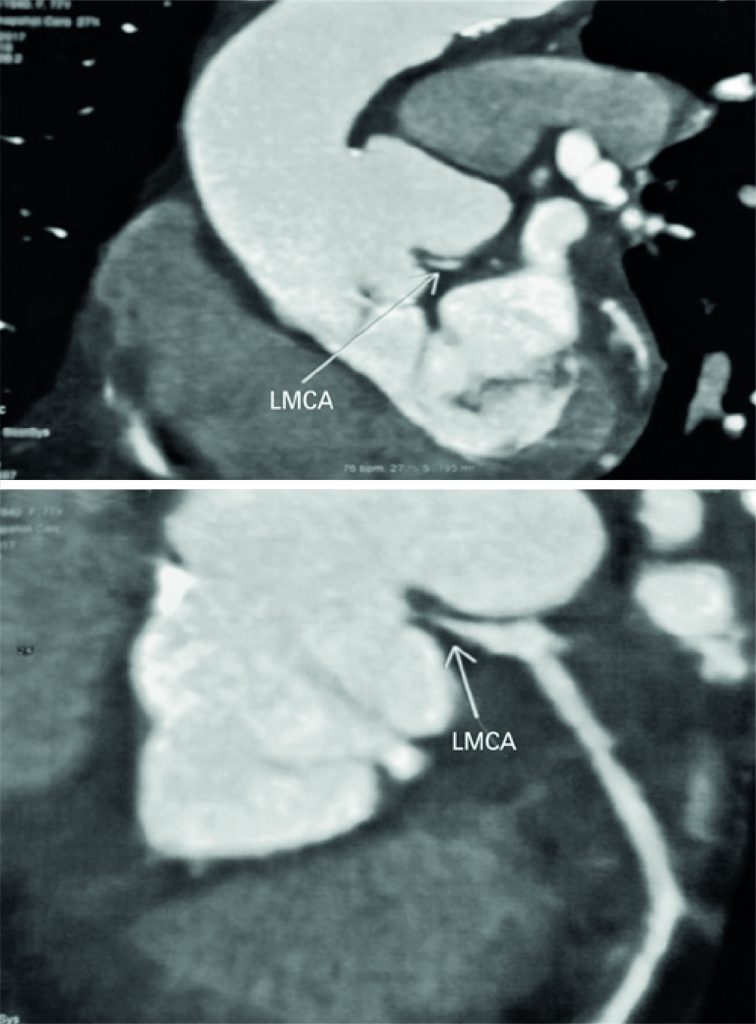

Figure 4

Computed tomography angiography showing extrinsic compression of the left main coronary artery. LMCA: left main coronary artery.